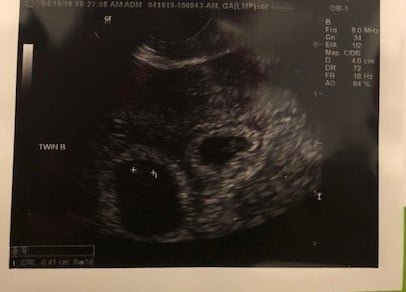

Found out yesterday, I am having twins.. EDD 12.7.19